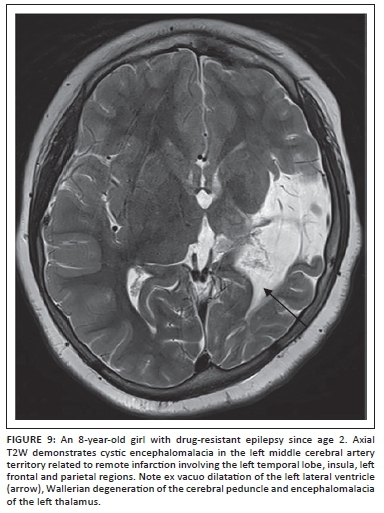

Based on the recommendations by consensus panels of the ILAE3 and the author's personal experience, the following MRI protocol sequences are recommended in children with epilepsy, irrespective of the strength of the MRI scanner (Box 1).